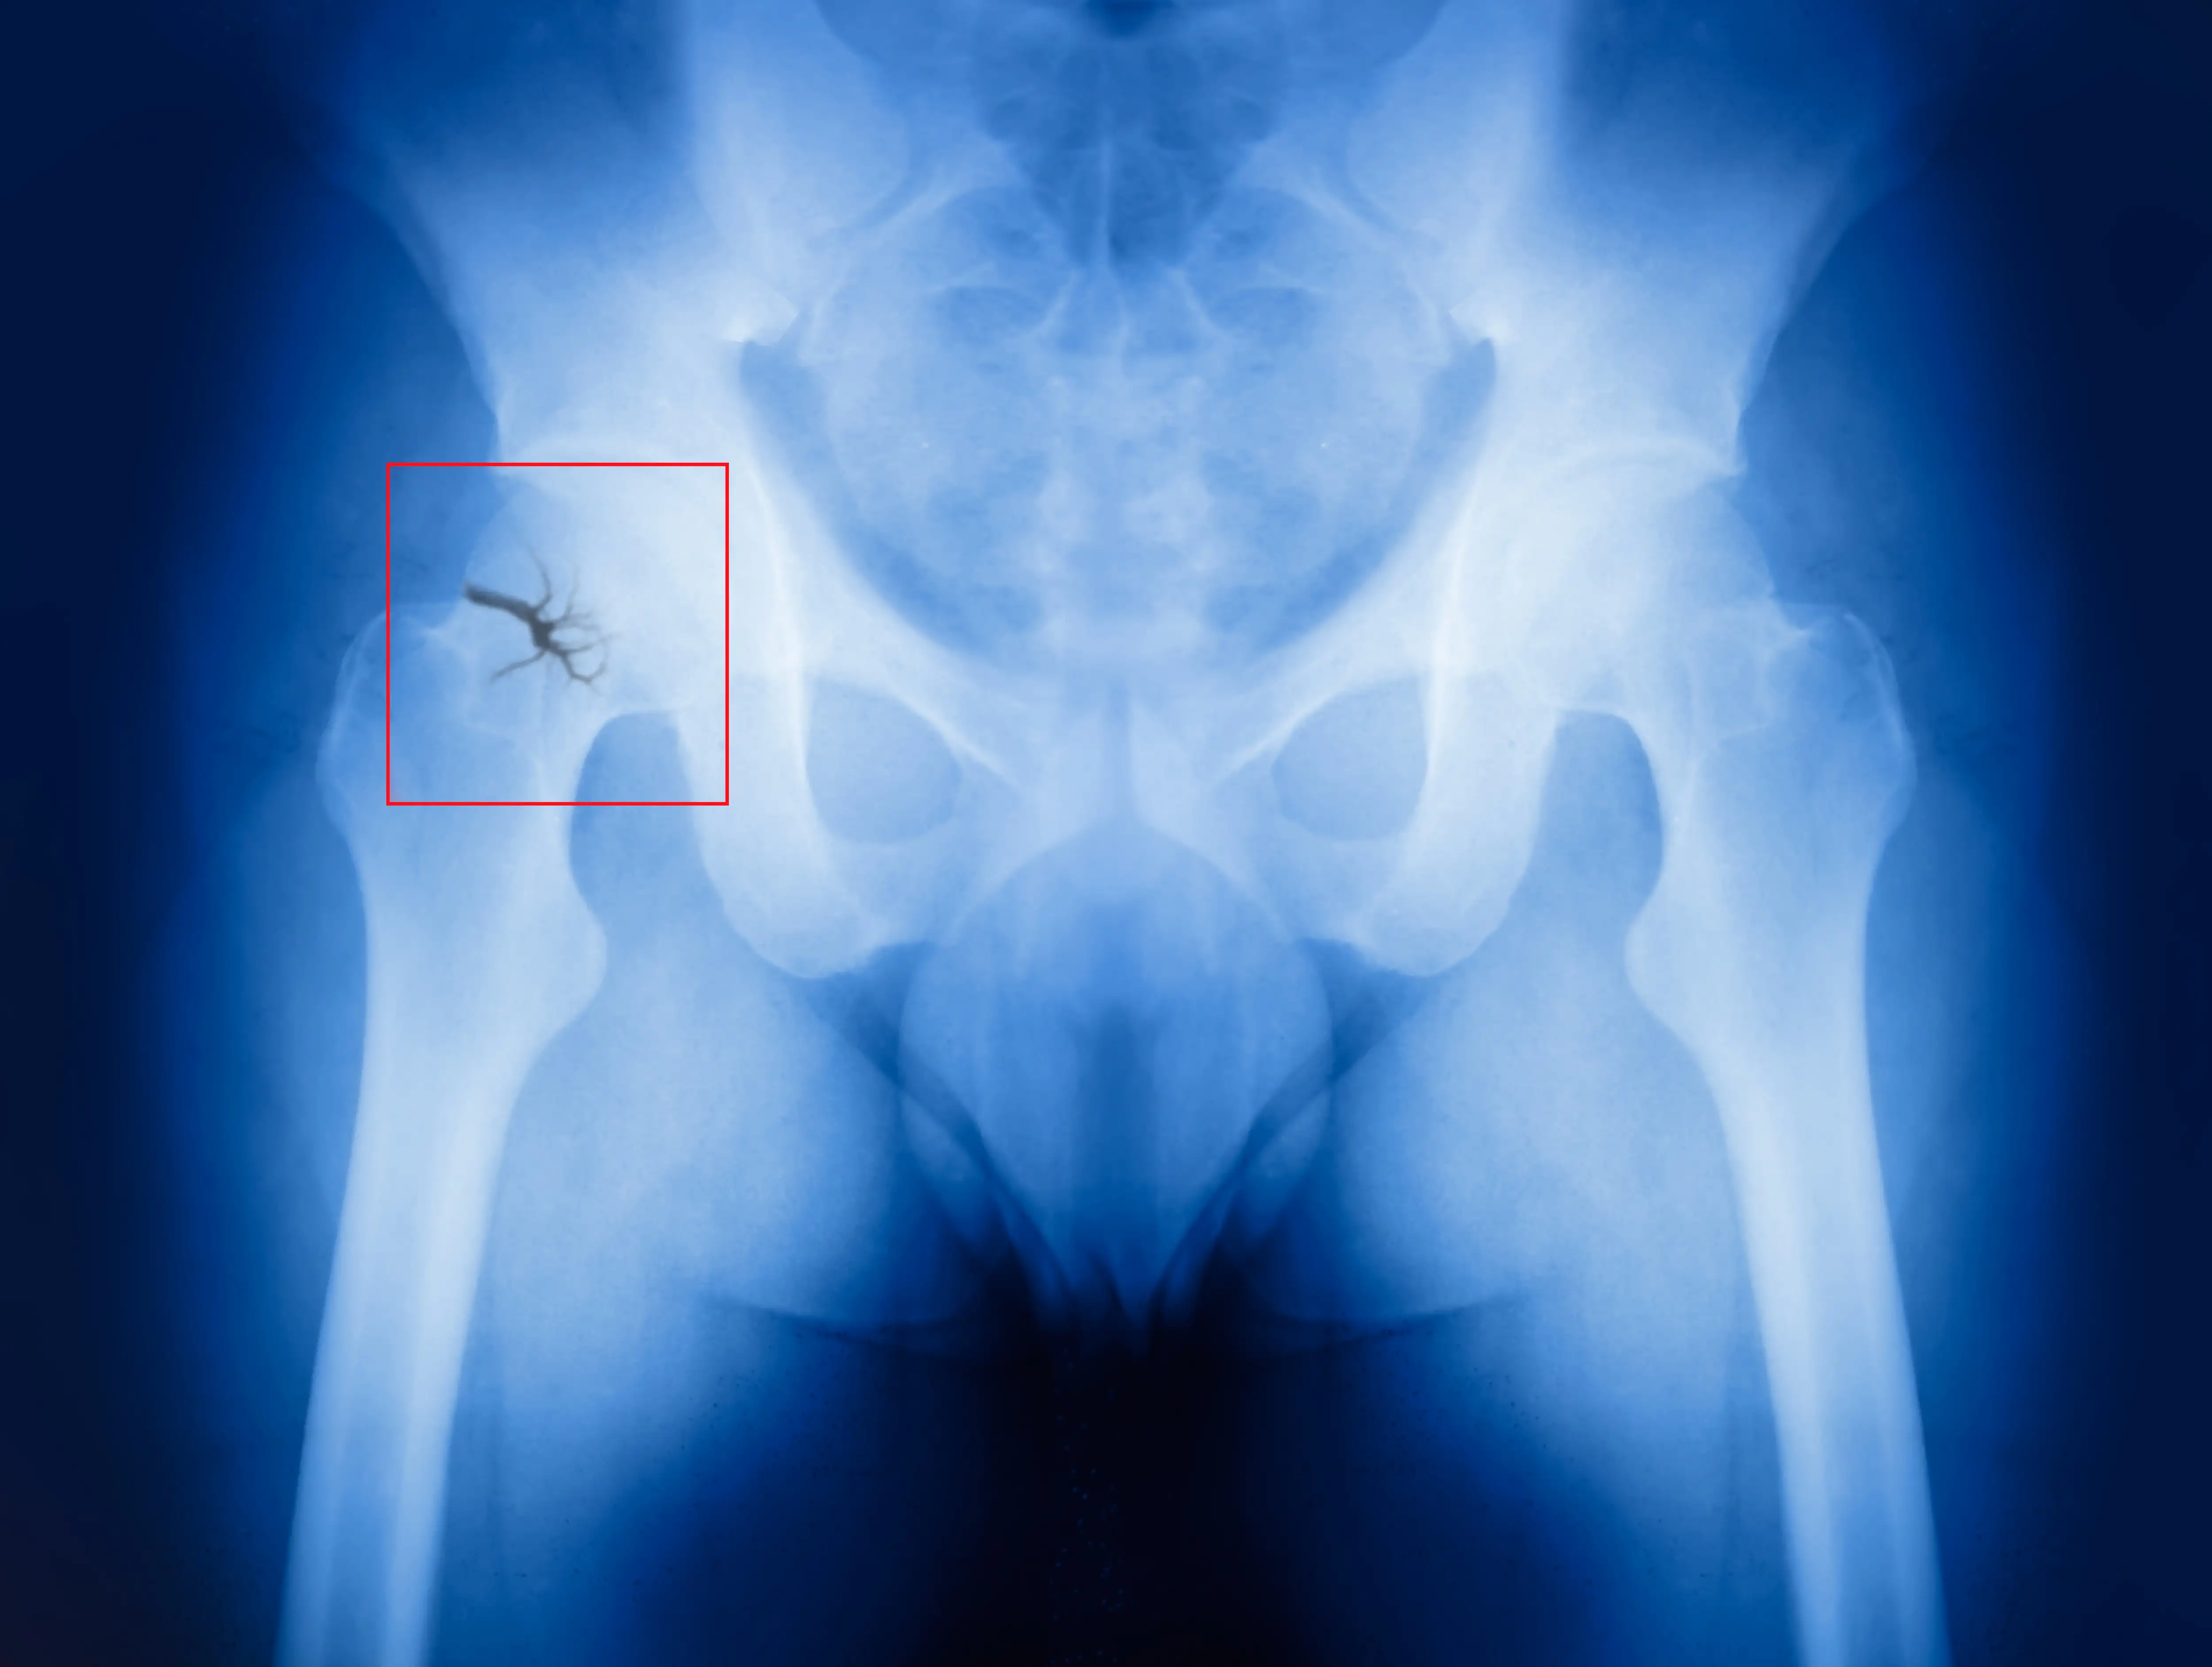

Patients with intertrochanteric fractures admitted to the emergency ward who took Ketorolac alone or in conjunction with magnesium sulphate infusion experienced remarkable pain reduction; however, the combination therapy produced better results, as elucidated from a randomized clinical trial. The purpose of the study was to compare the effectiveness and side effects of Ketorolac combined with placebo and Ketorolac combined with magnesium sulphate to relieve intertrochanteric fracture pain.

A total of 60 patients with intertrochanteric fractures were segregated into two groups: (A) Ketorolac (30 mg) with placebo (n = 30), and (B) Ketorolac (30 mg) + Magnesium sulphate (15 mg/kg) (n = 30). At baseline and 20, 40, and 60 minutes after the interventions, hemodynamic parameters, complications (nausea and vomiting), and pain score using the visual analogue scale (VAS) were measured. The groups' additional morphine sulphate needs were contrasted.

Except for the baseline assessments, all the evaluations revealed remarkably decreased pain intensity in the magnesium sulfate/Ketorolac group. Regarding hemodynamic measurements and complaints of nausea and vomiting, the two groups did not vary. Even while there was no difference in the frequency of subsequent morphine sulphate needs across the groups, those receiving Ketorolac/placebo treatment had considerably larger morphine sulphate doses.  Additional studies are highly recommended.